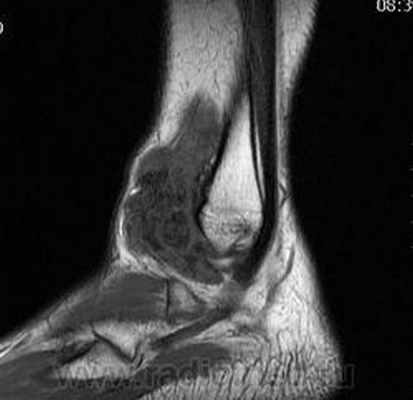

Пигментный виллёзонодулярный синовит - редкое заболевание с доброкачественным течением, характеризующееся пролиферативными изменениями синовиальной оболочки, отложением гемосидерина, образованием ворсинок, паннуса. Две разновидности: виллёзонодулярный бурсит и виллёзонодулярный тендосиновит. Частота - 2 на I 000 000. Преобладающий возраст • Виллёзонодулярный бурсит - 30-40 лет • Виллёзонодулярный тендосиновит -50-60 лет. Преобладающий пол - женский. Этиология. В 30% случаев развитию синовита предшествует травма сустава. Патоморфология. Пролиферация клеток синовиальных оболочек с образованием узлов, содержащих клеточный инфильтрат из фибробластов, лимфоцитов, макрофагов с жировыми включениями. Клиническая картина • Виллёзонодулярный бурсит -моноартрит. Чаще всего (80% случаев) поражается коленный сустав, реже - (с убывающей частотой) тазобедренный, голеностопный и плечевой суставы • Виллёзонодулярный тендосиновит - образование узелков в мышечных сухожилиях и связках сустава. Лабораторные исследования • Увеличение СОЭ • Синовиальная жидкость ксантохромная, с примесью крови • Биопсия синовиальной оболочки: узловая пролиферация, гемосидероз, инфильтрация мононуклеарными клетками. Рентгенологическое исследование • Остеопороз и наличие остеофитов нехарактерны • Артропневмография: множественные округлые дефекты наполнения синовиальной полости, обусловленные наличием узлов или гипертрофированных ворсинок синовиальной оболочки • МРТ - выявление гемосидерина и жировых включений. Артроскопия • Суставной хрящ приобретает коричневую окраску вследствие гемосидероза • Различной величины узлы коричневого цвета. Дифференциальный диагноз • Виллёзонодулярный бурсит • Липома - в аспиратах отсутствует ксантохромная жидкость • Остеоартроз - кисты возникают только на суставных поверхностях, подвергающихся нагрузке, тогда как при пигментном виллёзонодулярном синовите они образуются на всех суставных поверхностях. Остеофи-ты, напротив, более типичны для остеоартроза • Воспалительные арт-ропатии, дебютирующие моноартритом, - ревматоидный артрит, туберкулёзный артрит, анкилозирующий спондилоартрит и др. • Виллёзонодулярный тендосиновит - панглии (околосухожильные кисты): аспираты ганглиев содержат гелеподобную жидкость. Лечение хирургическое • Виллёзонодулярный бурсит • Тотальное иссечение синовиальной оболочки, вероятность рецидива заболевания составляет 25-40% • Лучевая терапия • Виллёзонодулярный тендосиновит - иссечение кист. Синоним. Синовит геморрагический МКБ. М12.2 Ворсинчато-узелковый (виллонодулярный) синовит (пигментный)

- лучевой диагностике (RÖ, МРТ);

Рентген и Артроскопическая картина СХС коленного сустава, при урогенной этиологии (рис. 2-3).![]()

Рис. 5. А. Артроскопическая картина коленного сустава, при пигментно-ворсинчатом узелковом синовите (ПВУС). Б. После артротомии сустава.

В. Состояние хрящевого покрова. Хрящевой покров бедра и надколенника пропитан гемосидерином.